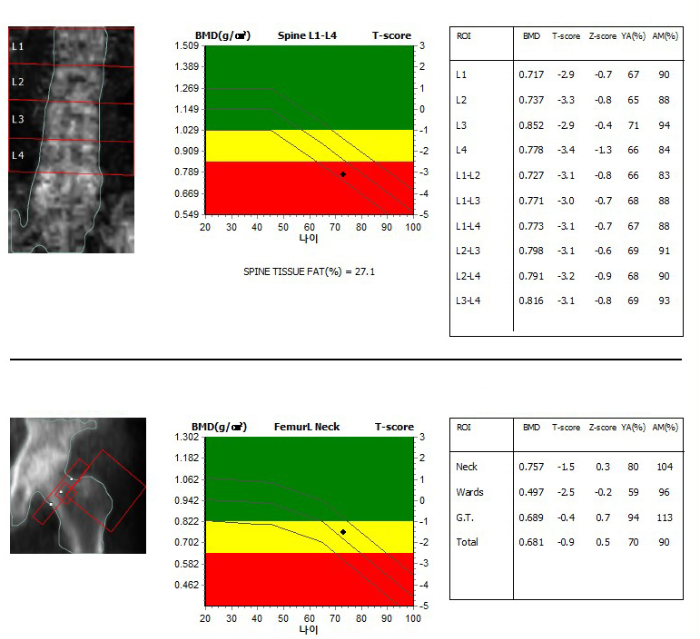

지금 보이는 사진이 대다수의 사람들이 받고 있는 골밀도 검사 사진입니다. 골밀도는 뼈의 건강을 확인할 수 있는 가장 대표적인 검사입니다. 최근에 건강검진이 보편화되면서 많은 사람들이 검진으로 골밀도를 받고 있습니다. 많은 사람들은 골밀도를 받고 자신의 뼈가 얼마나 나쁜지 그리고 약물 치료가 필요한지에 대해서 궁금해하지요. 골밀도에서 뼈 건강을 확인하는 핵심은 T score (T 점수)입니다. 본인의 골밀도 검사표를 확인하였을 때 T 점수가 -2.5보다 낮게 나오는 부위가 있다면 골다공증 여부에 대해 의사에게 물어보는 것이 필요합니다. 그리고 -1.0 아래로 나온 부위가 있다면 역시 골감소증의 가능성이 있습니다. 골다공증 뿐만 아니라 골감소증부터 뼈는 약해지고 있다는 뜻으로 적절한 치료와 회복이 필요합니다. 지금 보이는 사람 같은 경우 T- score가 -3.0 미만이 더러 보입니다. 이는 척추의 심한 골다공증이 있음을 뜻합니다.